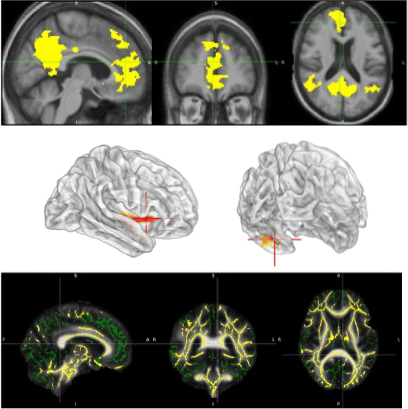

Functional MRI (fMRI) is a high-spatial-resolution non-invasive neuroimaging technique used to visualize brain activity by detecting Blood Oxygenation Level Dependent (BOLD) signals. These signals originate from dynamic changes within tissue vasculature due to alterations in blood flow, volume, and oxygenation, reflecting neural activity. There are two main types: task-based fMRI (tb-fMRI), which measures activation during specific tasks, and resting-state fMRI (rs-fMRI), which identifies intrinsic connectivity networks (ICNs) or resting-state networks (RSNs) without a task. It helps to identify areas of altered brain activation and functional connectivity, providing insights into a variety of neurological and neuropsychological conditions.

Diffusion Tensor Imaging (DTI) is an advanced structural MRI technique that provides detailed visualization of brain anatomy, particularly focusing on white matter integrity. It can detect structural abnormalities and physical cortical disconnections by analyzing the anisotropic diffusion of water molecules. This technique helps define the anatomy of normal white matter tracts and identifies changes caused by various neuropathological processes. DTI is an ideal tool for investigating white matter and its participation in cognitive and emotional functions. DTI helps understand the brain's structural connectivity that underpins functional networks.

"F-fluorodeoxyglucose (FDG) brain positron emission tomography (PET) is used to map glucose metabolism throughout the brain. FDG is a radiotracer that functions as a glucose analogue. The brain – as an obligate glucose user – preferentially accumulates FDG in its tissues, where patterns of FDG uptake reflect neuronal and synaptic activity. The radiotracer emits positrons and produces annihilation photons, which are detected by the PET scanner to generate metabolic images. An integrated computed tomography (CT) scanner provides anatomic data for improved morphologic correlation. PET/CT abnormalities in the brain typically represent underlying pathologies, such as epileptogenic foci, tumors, vascular lesions, and neurodegenerative diseases."

Image processing and analyses are predominantly conducted using MATLAB and Python. External plugins, including SPM25 and CAT12, facilitate the preprocessing of sMRI, fMRI, and PET images. The preprocessing pipeline encompasses segmentation, slice timing correction, motion correction, coregistration, normalization, and smoothing. FSL, a Python-based library, assists in the preprocessing and analysis of dMRI and fMRI. Additionally, MRIcron is employed for image visualization and comparison.

Statistical analyses are employed to compare group differences. Structural differences are assessed using voxel-based morphometry, surface-based morphometry, and deformation-based morphometry. Functional differences are measured through seed-based correlation analysis and independent component analysis. Diffusion tract measurements are compared via tract-based spatial statistics and voxelwise statistics. PET images are analyzed using standard uptake value measurements.

In this stage, images are processed for motion correction, denoising, smoothing, modulation, and alignment between modalities

Functional MRI

DTI

FDG-PET